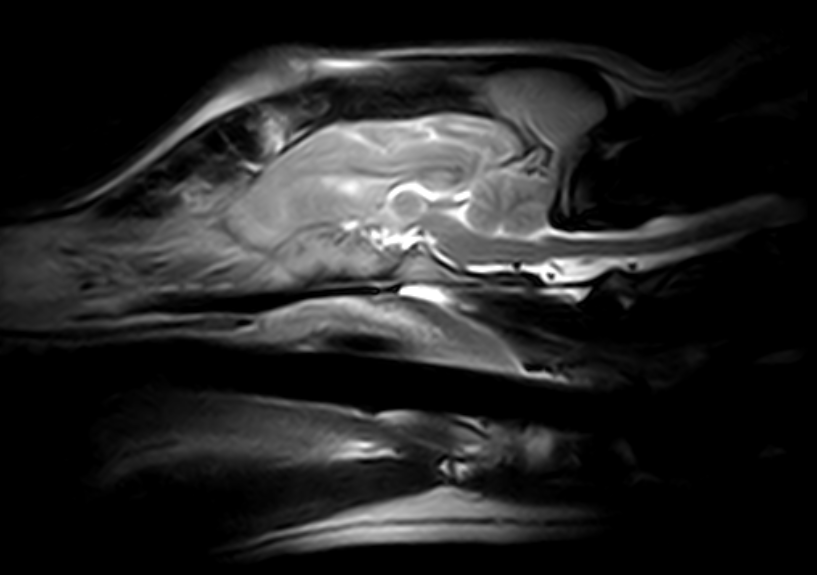

Imágenes de Calidad Premium

VET MR GRANDE

IMÁGENES CLÍNICAS

En la sección de imágenes clínicas, destacamos la precisión y claridad de nuestros estudios, respaldados por un equipo de radiólogos especializados en medicina veterinaria. Nos enorgullece ser un aliado confiable para veterinarios y clínicas, brindando un servicio rápido y eficiente para ayudar en la toma de decisiones clínicas fundamentadas.

Utilizamos resonancia magnética para obtener imágenes detalladas de tejidos blandos, articulaciones y el sistema nervioso central, permitiendo diagnósticos más precisos.